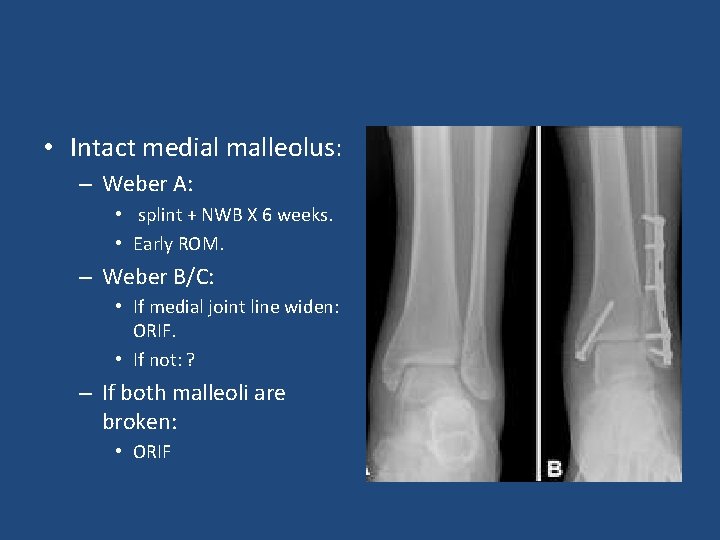

• Intact medial malleolus: – Weber A: • splint + NWB X 6 weeks. • Early ROM. – Weber B/C: • If medial joint line widen: ORIF. • If not: ? – If both malleoli are broken: • ORIF